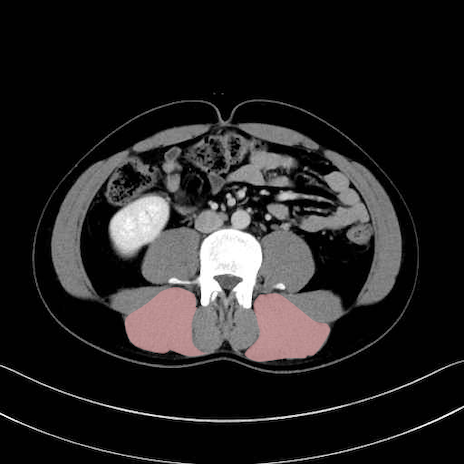

脊柱起立筋 (Erector spinae)

多裂筋 (Multifidus)

2. 腸腰筋群と骨盤底筋

大腰筋 (Psoas major)

腸骨筋 (Iliacus)

肛門挙筋 (Levator ani)